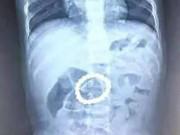

Ngày 16/4, bác sĩ Trần Sỹ, Phó giám đốc Bệnh viện Đa khoa huyện Hòa Vang (Đà Nẵng) cho biết, bệnh viện vừa tiếp nhận cấp cứu 32 học sinh Trường Tiểu học Hòa Khương 1 (xã Hòa Khương, huyện Hòa Vang) với các triệu chứng tức ngực, khó thở, buồn nôn, nhức đầu.

Sau khi sàng lọc, 5 trường hợp có biểu hiện nặng được chuyển đến Bệnh viện Phụ sản-Nhi, 13 trường hợp nhập khoa nhi của bệnh viện, 6 trường hợp theo dõi tại bộ phận cấp cứu và 8 trường hợp nhẹ được cho về nhà.